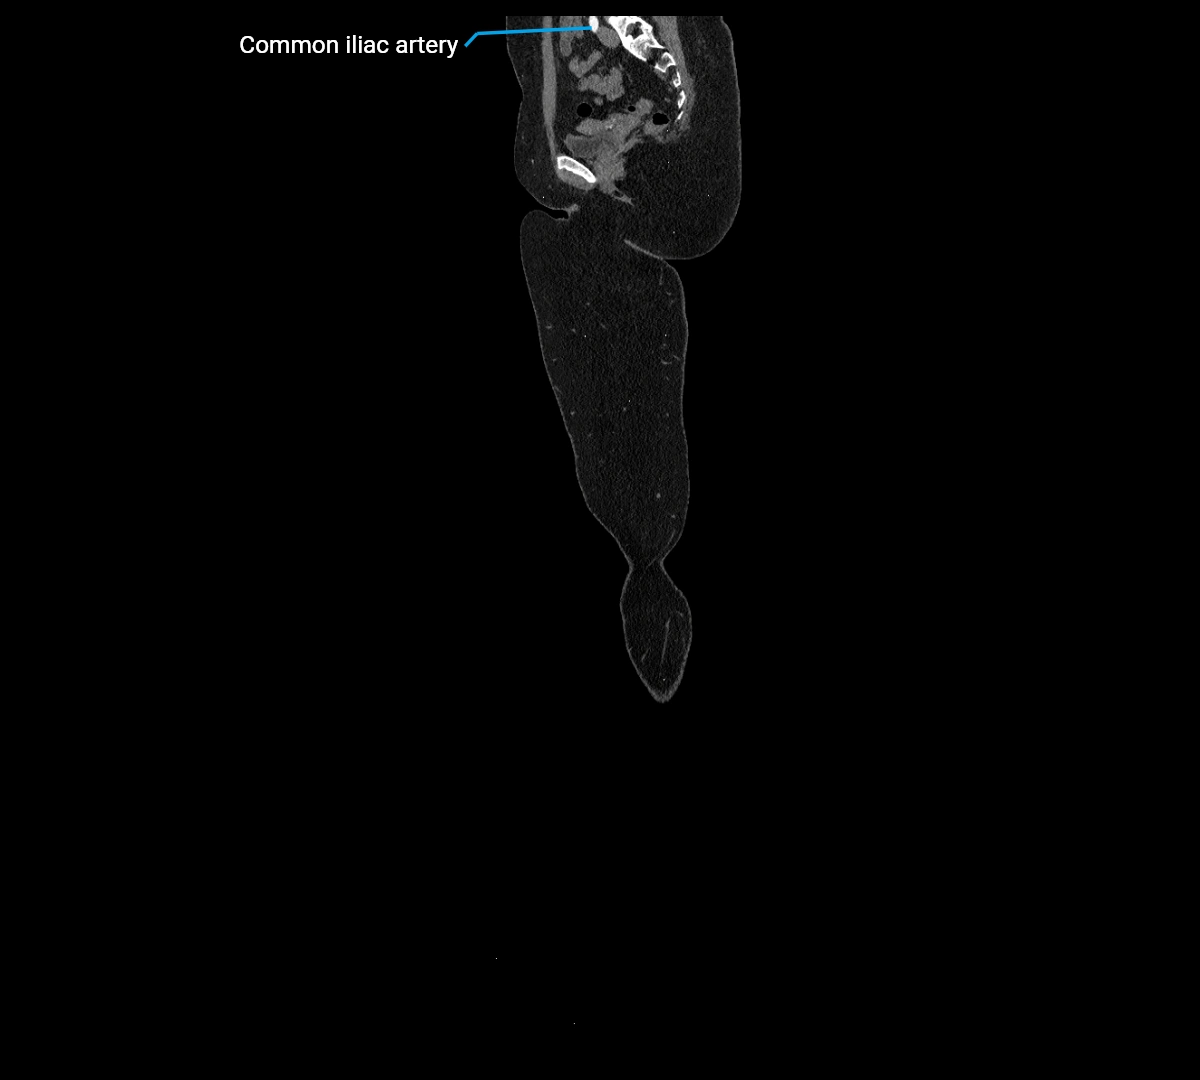

CT images

image